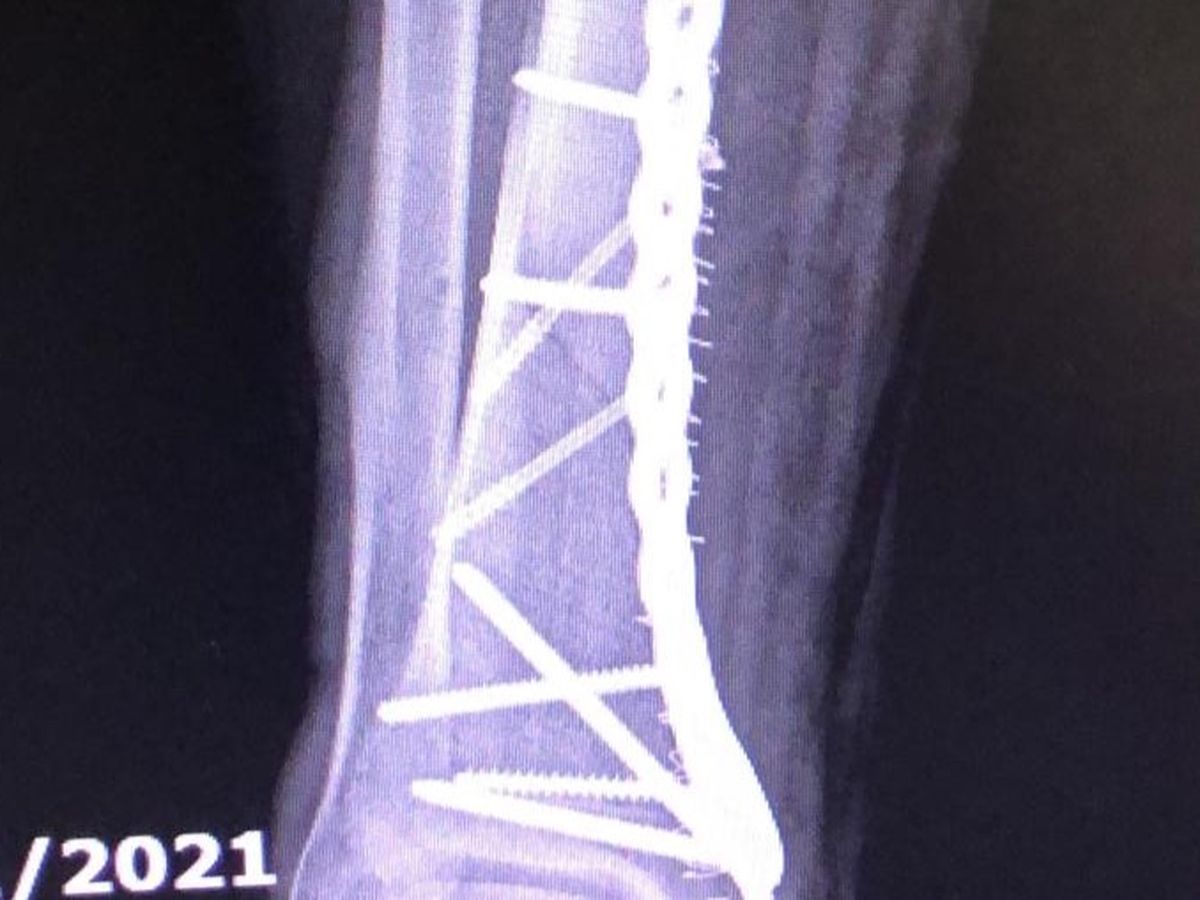

I was on my way to day to my second day of boot camp, only about 20mph and hit a patch of oil with no other vehicles or even people around and span off my bike and just putting my foot out to stop the spin snapped my leg in 3 places. My foot was turned around 180 degrees and flopping off the end of my leg like a grotesque fish.

Luckily a neighbour saw from window and rushed out to help. I knew enough to know not to move an inch. the police and ambulance came and were awesome. but until you get scanned and see a specialist there isn’t much they can do legally. So nearly 12 hours passed of a pain you can’t imagine. All I could think was ‘SERIOUSLY!? I literally just got out of hospital!’ I was mostly petrified of getting COVID again with patients coughing all around me. A shattered leg is like a birthday present compared to Delta.